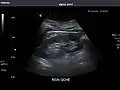

Aorta: Visualized portions normal in caliber, 16 x 15 mm.

Aorta